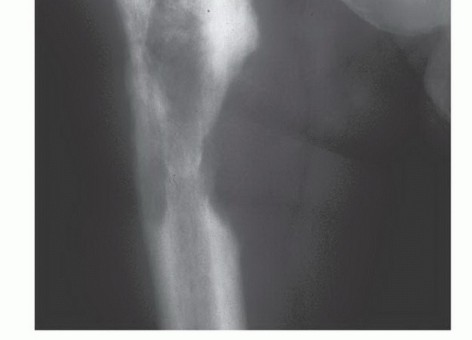

الشكل 2: أ. صورة أشعة سينية تظهر كسرًا مرضيًا في الورك لدى أنثى تبلغ من العمر 69 عامًا ولديها تاريخ معروف بسرطان الثدي. ب. أجريت عملية استبدال نصفي للورك خلال 24 ساعة من حدوث الكسر، ولكن صور الأشعة السينية بعد الجراحة أظهرت نقيلة إضافية أسفل طرف جذع الطرف الاصطناعي (ج) لم يتم اكتشافها بسبب سوء جودة صور الأشعة السينية قبل الجراحة ولأن صور الأشعة السينية للعظم بالكامل لم تُجرَ قبل الجراحة. د. بينما كانت لا تزال في المستشفى، عانت من كسر مرضي في تلك الآفة أثناء نقلها من سريرها إلى كرسي استلقاء.